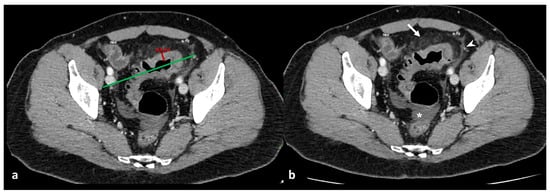

Figure 7. Axial (a) and coronal (b) contrast-enhanced CT images show an abscess near the sigmoid colon (arrowhead), located close to the uterine fundus (arrow). An axial unenhanced CT image (c) shows a 10 F pigtail catheter in the abscess collection.